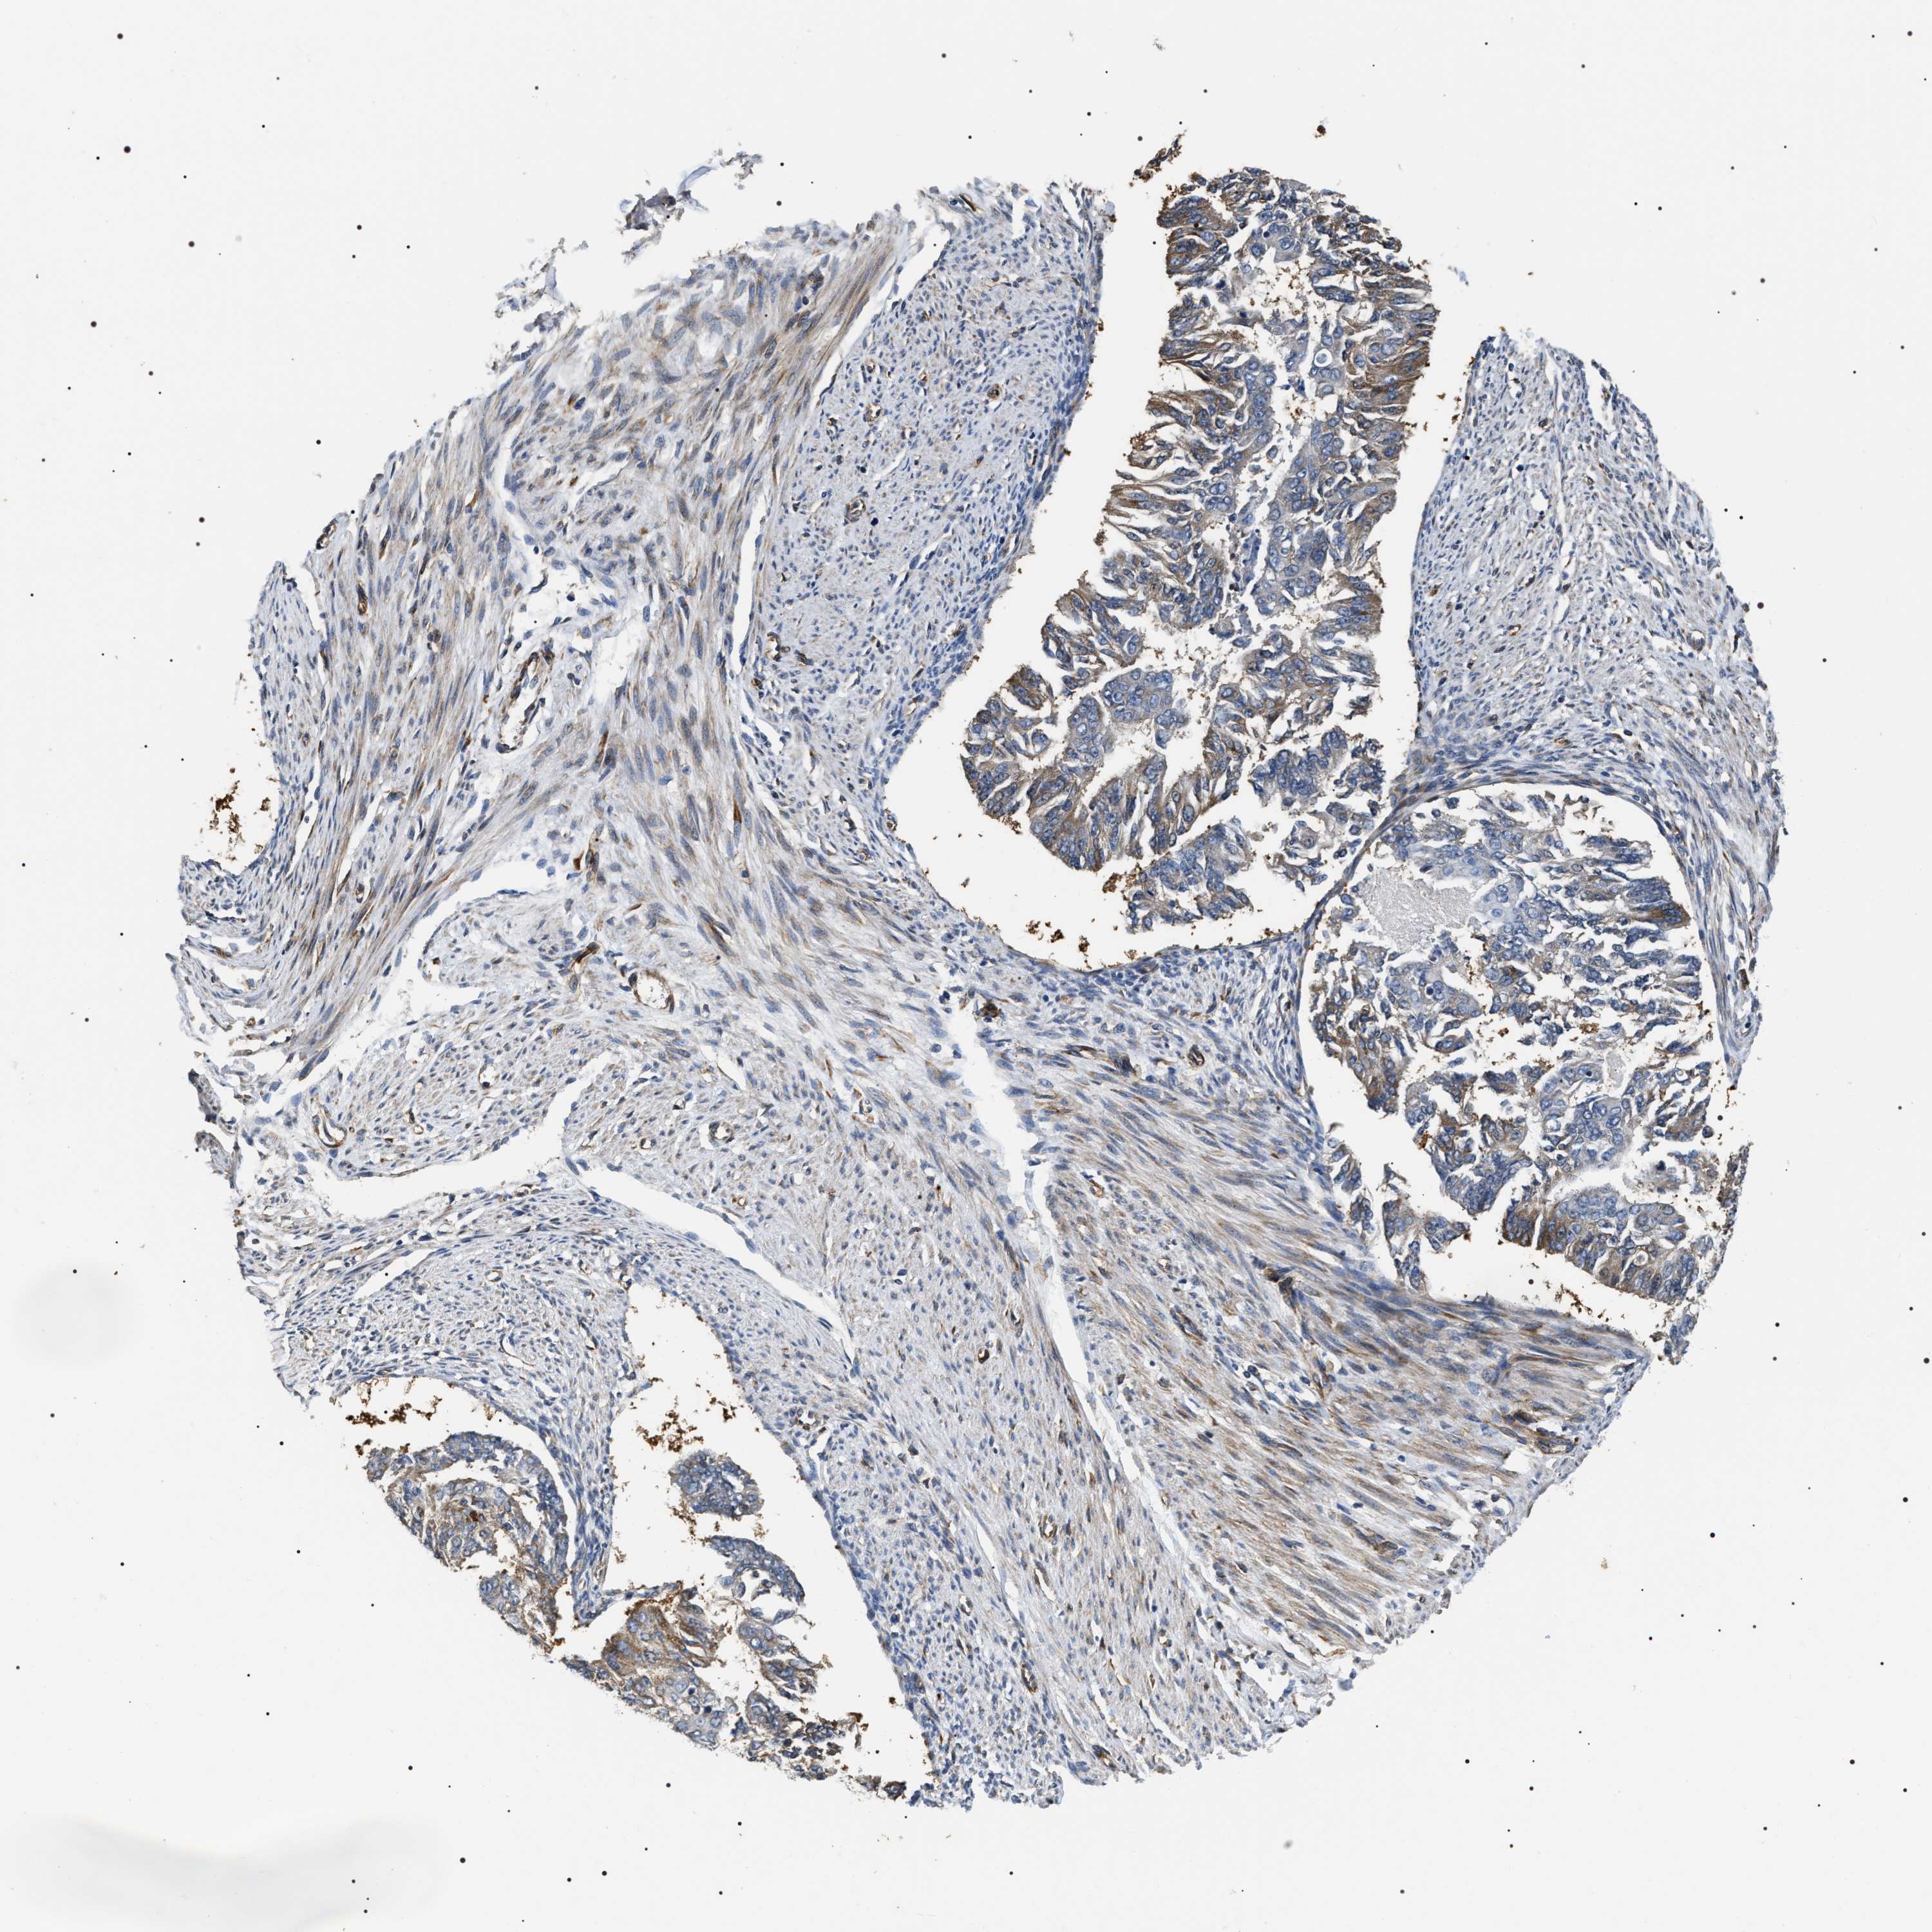

ENDOMETRIAL CANCER - Protein expressioni

A mouse-over function shows sample information and annotation data. Click on an image to view it in a full screen mode. Samples can be filtered based on level of antibody staining by selecting one or several of the following categories: high, medium, low and not detected. The assay and annotation is described here.

Note that samples used for immunohistochemistry by the Human Protein Atlas do not correspond to samples in the TCGA dataset.

Antibody stainingi

Antibody staining in the annotated cell types in the current human tissue is reported as not detected, low, medium, or high, based on conventional immunohistochemistry profiling in selected tissues. This score is based on the combination of the staining intensity and fraction of stained cells.

Each image is clickable and will lead to virtual microscopy that enables deeper exploration of all samples and also displays staining intensity scores, fraction scores and subcellular localization as well as patient and tissue information for each sample.

Antibody HPA020386

Staining

High

Medium

Low

Not detected

Intensity

Strong

Moderate

Weak

Negative

Quantity

>75%

75%-25%

<25%

None

Location

Nuclear

Cytoplasmic/membranous

Cytoplasmic/membranous,nuclear

Adenocarcinoma, NOS

Adenoma, NOS